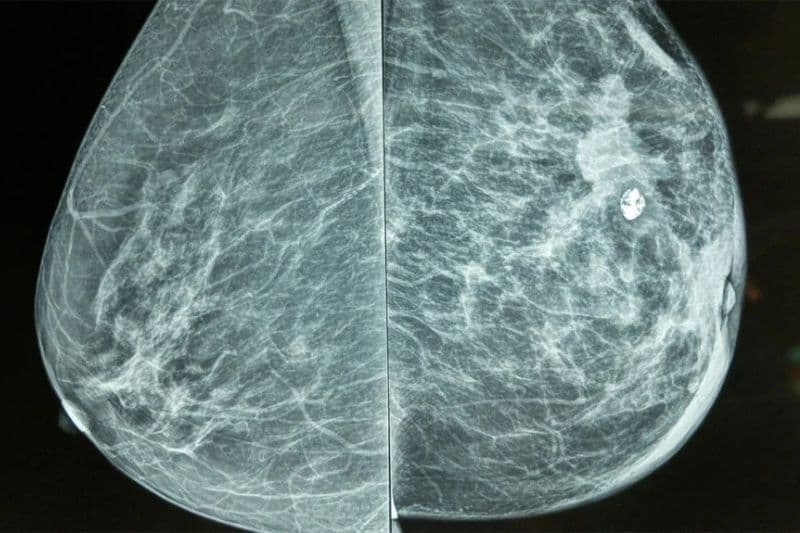

Tầm soát định kỳ bằng phương pháp chụp nhũ ảnh giúp giảm tới 40% tỷ lệ tử vong ở phụ nữ từ 40 đến 84 tuổi. Phương pháp này cho phép phát hiện những khối u siêu nhỏ mà mắt thường hoặc việc tự khám bằng tay không thể nhận ra. Khi phát hiện ở giai đoạn sớm, bệnh chưa kịp lan rộng, giúp quá trình điều trị đạt được hiệu quả tối ưu nhất.